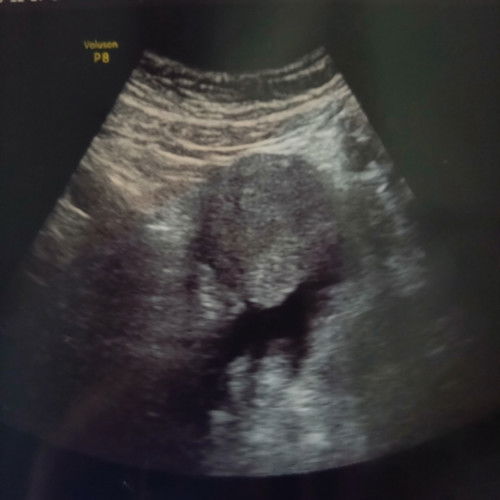

Kehamilan 4 minggu kantong rahim belum kelihatan, ada cairan di luar rahim, diminta periksa lagi bbrp minggu untuk memastikan ada kantung rahim atau memang hamil ektopik. Posisi lagi pulkam ke rumah org tua, sedangkan sy domisili dan kerja d luar kota dgn waktu perjalanan 15- 17 jam jalur darat (mobil). Riwayat keguguran 2 bulan yang lalu, di usia kandungan 8 minggu, tidak dikuret (diagnosis janin tidak berkembang). Kondisi sekarang sedikit nyeri pinggang, dan terkadang agak nyeri di perut bawah. Bingung banget harus lanjut pengobatan d kota orang tua dikelilingi keluarga atau di perantauan berdua suami aja. Aman ga ya, menempuh perjalanan 15 jam via bus dengan kondisi seperti ini? 😟 #seriusnanya #ingintahu #pleasehelp